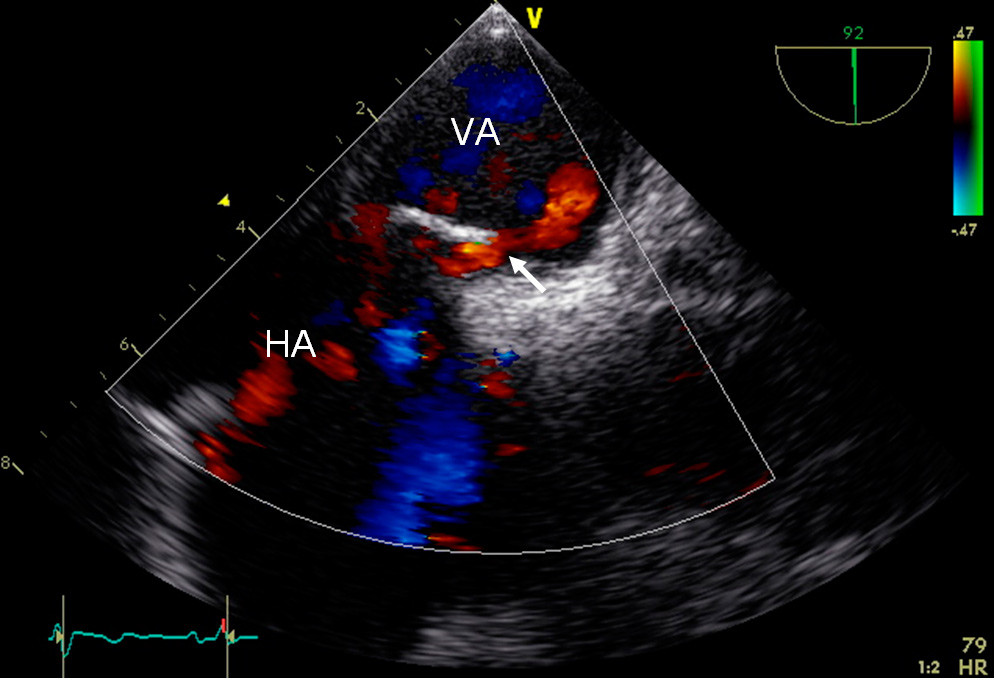

Cerebral computer tomography (CT) performed at the local hospital revealed «hyperdense right middle cerebral artery sign» and cerebral CT angiography revealed an embolic occlusion at the bifurcation of the right middle cerebral artery. A cerebral CT the following day documented infarction of the basal ganglia in the right hemisphere, and a CT angiogram showed complete recanalisation of the right middle cerebral artery. Transoesophageal echocardiography (TEE) with saline contrast two days after admission showed patent foramen ovale with a diameter of 4 mm (Fig. 1).

Figure 1  Transoesophageal echocardiogram with saline contrast two days after admission shows right-to-left shunt from right…

Figure 1 Transoesophageal echocardiogram with saline contrast two days after admission shows right-to-left shunt from right atrium (HA) to left atrium (AV) in connection with a Valsalva manoeuvre, consistent with patent foramen ovale (arrow). Photo: Department of Cardiology, Oslo University Hospital, Rikshospitalet